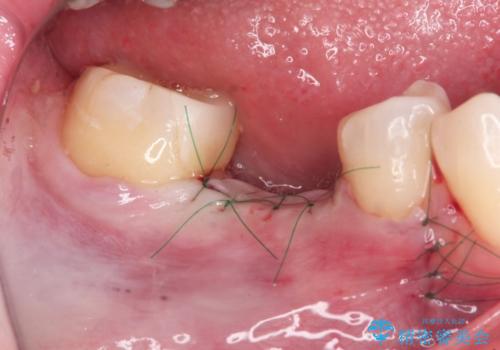

- 44万円(インプラント・チタンカスタムアバットメント・ジルコニアクラウン・仮歯)費用は治療当時の料金となります

安定し、長く使用できるようなインプラント治療を実践するため、骨の増成をインプラント埋入と同時に行いました。